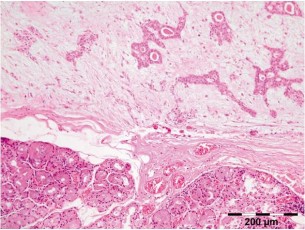

Hình 1.5. Mô bệnh học u hỗn hợp tuyến lệ

Các cấu trúc ống được bao quanh bởi tế bào cơ biểu mô trên nền mô đệm dạng sụn - nhày (H & E x 100)

Nguồn: O’Rourke và cộng sự (2020)39

Vi thể: Về mặt mô bệnh học các đặc điểm đặc trưng là gồm các cấu trúc giống ống dẫn được phủ biểu mô và lớp ngoài là các tế bào cơ biểu mô. Kích thước của lòng ống có thể thay đổi và có thể chứa các chất cô đặc, ưa toan, dương tính với PAS, có tích lũy chất nhầy, ưa kiềm giữa các tế bào cơ biểu mô và giữa các cấu trúc ống. Đôi khi còn thấy các ổ dạng sụn hoặc canxi hóa. Các tế bào biểu mô có thể hình thành các dải đặc biệt hóa vảy và tạo thành các nang. Trong một số trường hợp, khối u có các tế bào cơ biểu mô hình thoi, khác biệt rõ ràng với các tế bào biểu mô ống hình vuông, ưa toan. Lắng đọng các sợi fibrin ngoại bào giống như chất dạng tinh bột và các cấu trúc tinh thể oxalate hoặc tyrosine có thể được tìm thấy trong mô đệm u. Nếu u tái phát thì thường có cùng đặc điểm phát triển và cấu trúc mô bệnh học như u nguyên phát.